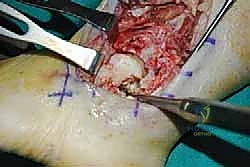

2. الشق الجراحي والوصول للمفصل

يقوم الدكتور هطيف بعمل شق جراحي دقيق (غالباً من الجهة الجانبية أو الأمامية) للوصول إلى مفصل الكاحل مع الحفاظ التام على الأوعية الدموية والأعصاب الدقيقة باستخدام تقنيات الجراحة الميكروسكوبية التي يبرع فيها.

3. استئصال العظام التالفة (Talectomy)

في حالات "شاركو" المتقدمة، تكون عظمة الكاحل (Talus) مجرد فتات عظمي ميت (Avascular Necrosis). يتم استئصال هذه العظمة بالكامل، بالإضافة إلى إزالة أي غضاريف متبقية من أسفل قصبة الساق وأعلى عظمة الكعب لضمان تلامس عظمي حيوي ونظيف.